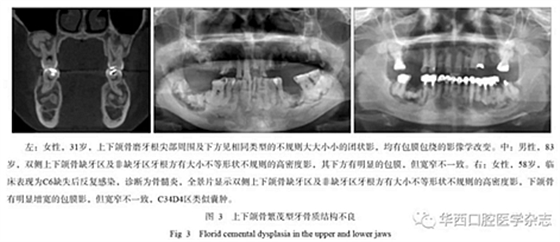

2.4 上、下頜骨均發(fā)生

這類改變可稱為“繁茂型牙骨質結構不良”,簡單地理解就是在上下頜骨只要有牙的地方都可以發(fā)生[1]。由于牙骨質小體無序混亂的生長,導致牙和頜骨出現(xiàn)相關的血供問題,臨床上常常發(fā)生骨髓炎改變,甚至頜骨局部膨大類似腫瘤,病程很長,治療效果也不好。繁茂型牙骨質結構不良的影像學特征是上下頜骨均出現(xiàn)多數(shù)的高密度小團片狀影,周圍有包膜包繞,骨皮質可變薄,繼發(fā)感染時可出現(xiàn)類似死骨的征象,而向外膨脹的時候就表現(xiàn)為類似腫瘤樣改變(圖3)。